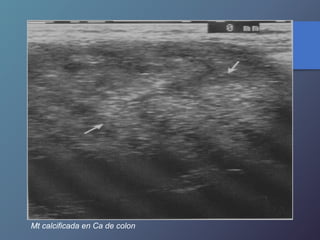

MT calcificadas:

• Presentan una ecogenicidad acentuada y

marcada sombra Acústica

• Frecuentes en adenocarcinoma de colon,

gástricos, TU. Pancreaticos, leiomiosarcomas,

neuroblastomas, cistadenocarcinomas,

teratocarcinoma ováricos.

Mt calcificada en Ca de colon

Mt calcificada enCa de colon